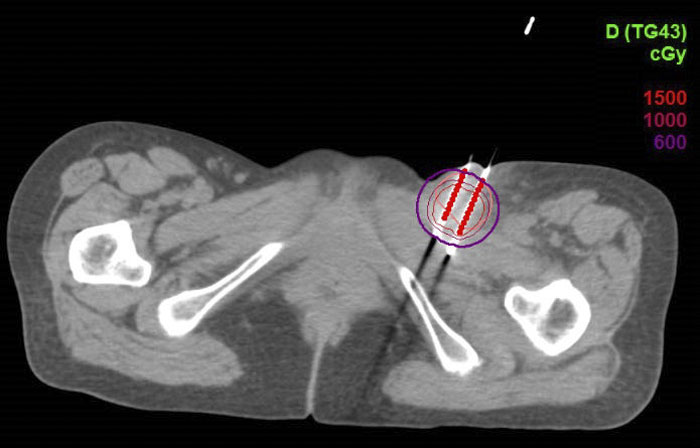

CT引導下的左側腹股溝淋巴結組織間插植劑量圖

該患者的淋巴結轉移病灶在淺表,外照射劑量無法達到根治效果,且易出現皮膚破潰等放射損傷。選擇CT引導下無痛組織間插植近距離放療,可實時調整金屬針的進入方向和位置,針對腫瘤給予更適形、更精準的放射治療,在根治腫瘤的同時有效減少了周圍正常組織的放射損傷。

CT引導下組織間插植近距離放療是依據腫瘤形態及范圍,制定插植針的排列及置入方向,將中空的金屬針在CT引導下直接插入腫瘤組織內,再進行CT掃描,在治療計劃系統中勾畫靶區,由物理師進行靶區劑量優化及危及器官限量。計劃完成后,通過傳輸管將插植針與放射源相連接;通過計算機控制,將放射源輸入插植針進行放射治療,待結束后,放射源回收到貯源器內,保證患者體內無放射源殘留。組織間插植使用銥192放射源,由于射線能量與距離成平方反比,可在腫瘤靶區內形成高劑量,而周圍正常組織劑量極低,從而實現最大限度的腫瘤殺傷,且非常安全。